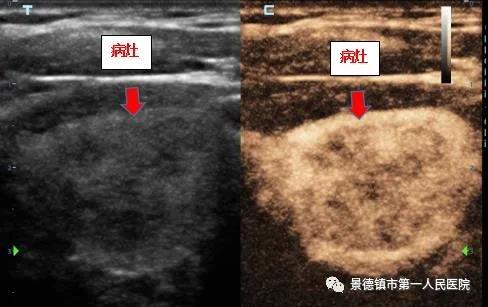

该患者为中年男性,因近期发现甲状腺有一约2.5*1.8*3.7cm的肿物,慕名来我院内分泌科要求行甲状腺微波消融手术,术前行甲状腺细针穿刺术,病理考虑为良性病变。有消融指征。内分泌团队遂为其行甲状腺微波消融术。 术前超声造影 术后超声造影提示还有少许组织残留,随即对其进行精准灭活。 术后再次行超声造影,肿瘤已完全灭活。 市一院内分泌科已成熟开展甲状腺肿瘤消融术2年余,现将超声造影技术辅助应用于微波消融术前评估及术后肿瘤灭活情况即刻评估,使得肿瘤“无处遁形”,大大提高了微波消融手术的“精准性”及“根治性”。